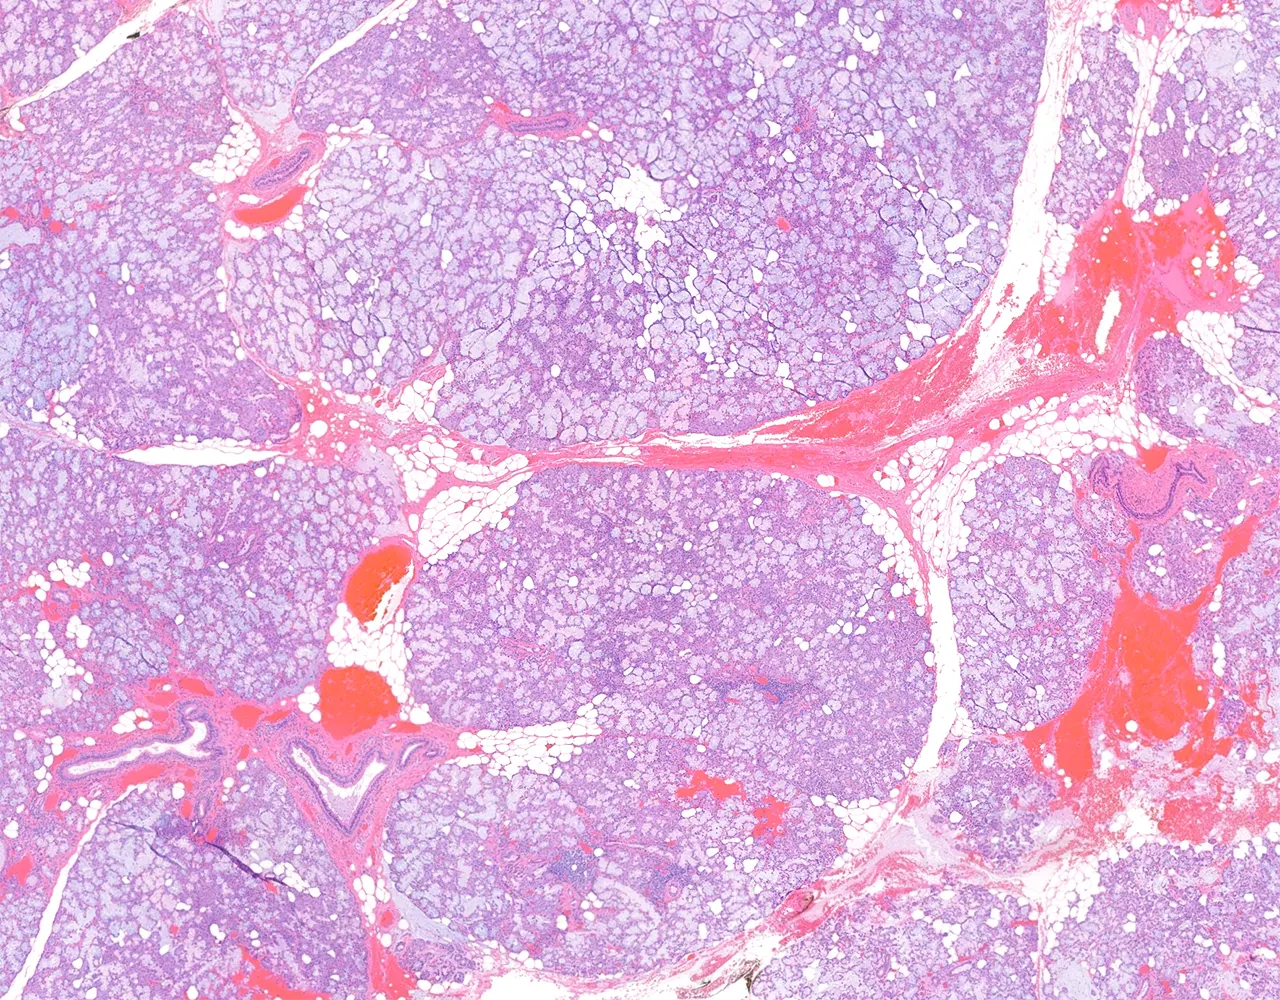

- The major salivary glands are paired organs and include the parotid, submandibular, and sublingual glands.

- They are compound tubuloacinar exocrine glands.

- Each gland is surrounded by a thin capsule.

- The capsule extends septa into the glandular parenchyma, dividing it into lobes and lobules.

- Microscopically, the functional structure of a salivary gland consists of secretory acini and a duct system.